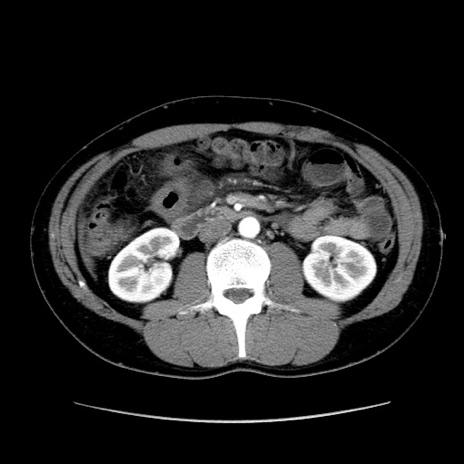

症例36(横断像)

【症例】20歳代 男性

【主訴】心窩部痛

【現病歴】今朝より上腹部痛あり。一旦軽快していたが再度出現したため救急要請。昨日夕に白身の魚を含む刺身を食べた。

【身体所見】BP 136/89mmHg、HR 74/min、BT 37.0℃、腹部:膨満、軟、心窩部に圧痛あり。反跳痛なし、筋性防御なし、腸雑音やや亢進あり。

【データ】WBC 17700、CRP 0.48